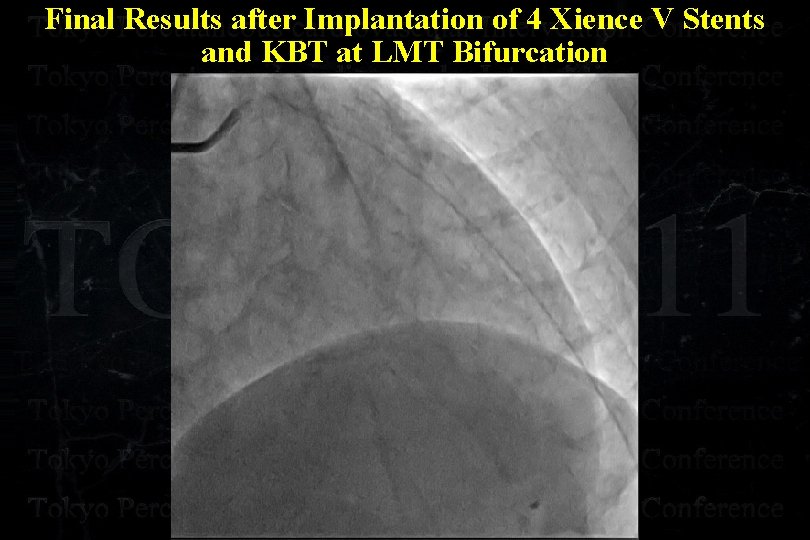

Final Results after Implantation of 4 Xience V Stents and KBT at LMT Bifurcation

Final Results after Implantation of 4 Xience V Stents and KBT at LMT Bifurcation

Final Results after Implantation of 4 Xience V Stents and KBT at LMT Bifurcation